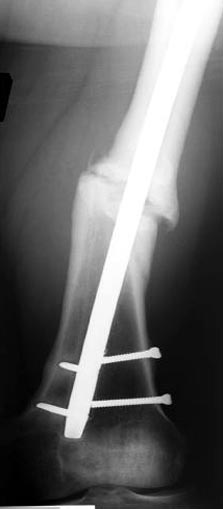

Снимки представлены: 1 мес; 3 мес; 1 год; 2 года, предоперационные и ротационная КТ грамма

Деформация:

Вальгус- 17 градусов

Рекурватум 5 градусов

Укорочение 2.5см

Ротационно 22 градусов внутренная

Смещение диафиза по поперечнику 75%

Аппарат Илизарова= Taylor spatial frame